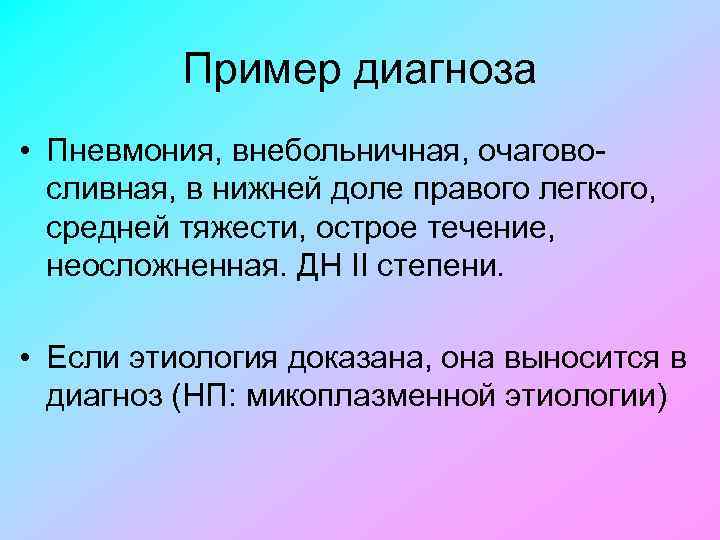

Острая внебольничная пневмония по МКБ-10: признаки и примеры